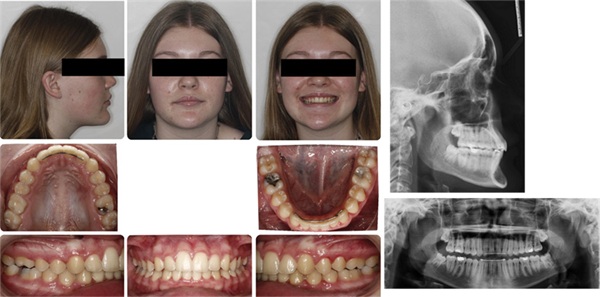

After treating Tara, 12-year-old Nicole and her mom came to my office. She had been through a brief early treatment with another practice, and their chief complaint was “excess overbite/flared front teeth.” Her presentation immediately brought Tara’s case to my mind (Figs. 5–9).

In my appraisal, Nicole presented a conundrum regarding maxillary incisor and lip position. Obviously, correction of the protrusive upper incisors to establish ideal labiolingual axial inclination was of primary importance in this case (to the patient and parents as well). However, I very much liked the presentation of her lips, and did not wish to reduce their A-P position.

I specifically asked Nicole and her mom about her lips in that initial meeting. I think that it is extremely important to do in cases that could involve significant A-P change of the maxillary incisors. It is my strong opinion that orthodontists should always discuss lip position in cases that involve maxillary incisor retraction.

Nicole and her mom stated that they would like her upper teeth “moved back” out of their protrusive position. I then asked if they liked her lip presentation, if they would like her lips “moved back,” and if so, how much. Their response was clear and without hesitation: They liked her lip position and would not like them to be retracted at all during treatment, if possible.

The other macro (facial) feature that added to the complexity for Nicole was her prominent chin. In my opinion, her excess chin projection was the single facial trait most out of aesthetic balance in this otherwise beautiful face. It was clear to me that there were two aspects of orthodontic treatment that could iatrogenically worsen this sensitive trait. First, any noticeable retraction of her lips would, by relation, act to further highlight this chin prominence. Second, any decrease in her lower one-third facial height would lead to counterclockwise rotation of the mandible and result in an even more forward position of that chin.

I felt confident that extracting two upper bicuspids (either first or second) would allow me to retract the protrusive upper incisors. I was concerned, however, that the total amount of retraction offered by those extractions could directly impact lip retraction more than desired. I was also concerned that extractions could tend to favor overall vertical closure both during treatment and posttreatment.1 Again, my goal during and after treatment for Nicole, because of excess chin prominence and her “square”/brachy frontal facial form, would be to limit any decrease in her lower one-third facial height.

For these reasons, based on her unique aesthetic presentation, I decided to opt for a nonextraction treatment plan for Nicole.

For Nicole, I preferred idealizing her excessive upper incisor labiolingual inclination while only mildly retracting their A-P position. Mechanically, this was achieved via inverting her four upper incisor brackets to reverse the labiolingual torque, conservative interproximal reduction (0.4 mm between each contact U3–3 and L3–3), mild arch expansion (Dynaflex Norris extra-broad NiTi wires), and Class II elastics. The case was treated in 22 months.

Evaluating the case from “outside-in,” I am satisfied posttreatment with the unique macro/facial features that needed to be controlled. Her pretreatment A-P lip position, which was favored by Nicole and her mom, was well preserved, with only very minimal reduction to her forward position. Additionally, Nicole’s lower one-third facial height slightly increased during this treatment (SN-GoGn and FMA increased by 2 degrees). The eruptive nature of the Class II elastics likely played a role in this (Figs. 7–8).

Also important to consider, Nicole is brachyfacial with well-developed masseters. She has a type of facial pattern that will naturally favor vertical closure with aging. The fact that we have met our aesthetic treatment goals while retaining her full complement of dentition to support the maintenance of her lower one-third facial height is, in my opinion, meaningful. The more she vertically closes over time, the more the dominant unaesthetic feature within her face (chin projection) becomes more dominant and the more “square” her frontal facial form becomes (as opposed to the more natural tapered/ovoid frontal facial shape which is associated with a more balanced lower 1/3 facial height).

Upper incisor labiolingual inclination (U1-SN) decreased from 129 to 107 degrees. It is also important to note that the Class II elastics also advanced her lower incisors significantly, IMPA increased from 89 degrees to 99 degrees.